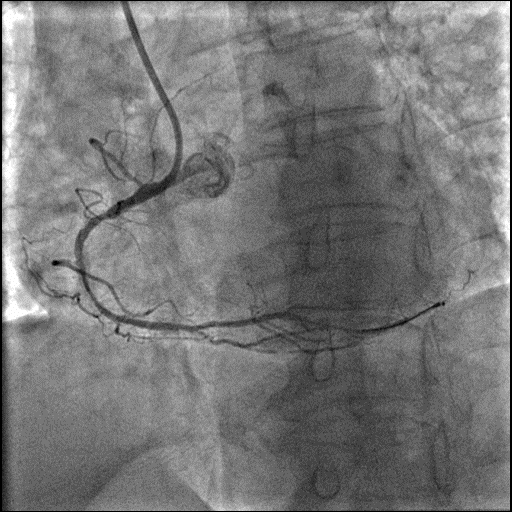

冠脉造影

左前降支近段、中段,狭窄程度50-70%,病变长度弥漫性,严重钙化,TIMIⅢ级:第一对角支开口病变,狭窄程度70-90%,病变长度局限性,TIMI Ⅲ级。

回旋支近段,狭窄程度70-90%,病变长度弥漫性,TIMI III级:回旋支远段,狭窄程度90-99%,病变长度弥漫性,TIMI III级;钝缘支,狭窄程度50-70%,病变长度管状性,TIMI III级。

右冠状动脉近段、中段、远段,狭窄程度70-90%,病变长度弥漫性,严重钙化,TIMI III级;

右冠状动脉后降支,狭窄程度70-90%,病变长度管状性,TIMI II级;后侧支,狭窄程度50-70%,病变长度弥漫性,TIMI III级。